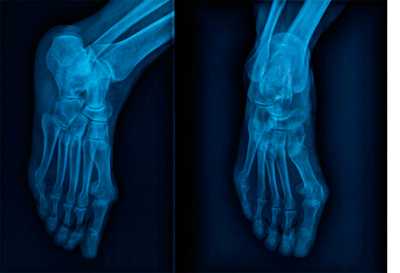

Информативность .снимков. На снимках видны кости предплюсны: таранная, ладьевидная, кубовидная и клиновидные, суставные щели между ними. Раздельно отображаются все кости плюсны и фаланг, видны их переднебоковые и зад небоковые поверхности. Прослеживаются рентгеновские суставные щели плюснефаланговых и межфаланговых суставов (рис. 449).

В этом случае снимки стоп в косых проекциях по сравнению с другими снимками являются наиболее информативными для выявления переломов плюсневых костей и фаланг (рис. 450, а, б).